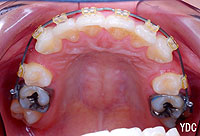

2期矯正に使用する透明ブラケット